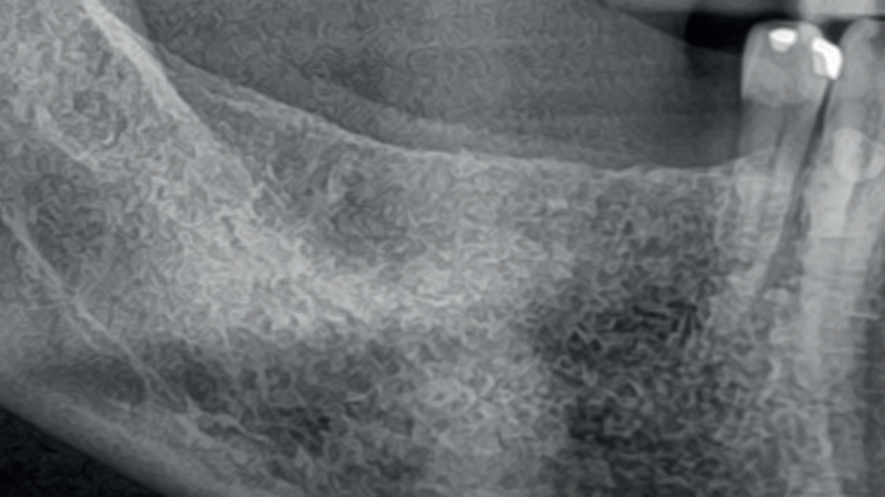

Ao serem instalados, os implantes que atingem um torque de inserção ≥ 32 Ncm podem ser imediatamente carregados com coroas unitárias de transição não oclusivas. Abaixo deste torque, ou em situações onde não desejamos correr riscos, em vez de uma coroa de transição, instala-se um cicatrizador personalizado contendo um perfil transmucoso com as mesmas características que a coroa provisória teria. Os objetivos dos cicatrizadores customizados nos casos de instalação do implante imediatamente após a exodontia são: selar o sítio cirúrgico respeitando o perfil do alvéolo de extração, estabilizar o coágulo sanguíneo e favorecer a regeneração óssea com o material substituto, evitar o colapso de tecidos moles durante o período de cicatrização e desenvolver um perfil de emergência protético ideal para a futura coroa sobre implante, baseado na anatomia do dente natural extraído, sem receber carga oclusiva.

Nos casos de instalação de implantes em regiões edêntulas, também é possível empregar cicatrizadores personalizados, desenvolvendo um perfil de emergência protético ideal para a futura coroa sobre implante, baseado na anatomia do dente natural ausente. Os dois procedimentos restabelecerão o perfil de emergência original do paciente durante a fase de cicatrização/osseointegração dos implantes, devolvendo a harmonia dentogengival, com a recuperação das papilas interdentais e a reconstituição do arco gengival côncavo, com altura adequada da margem em relação aos dentes adjacentes.